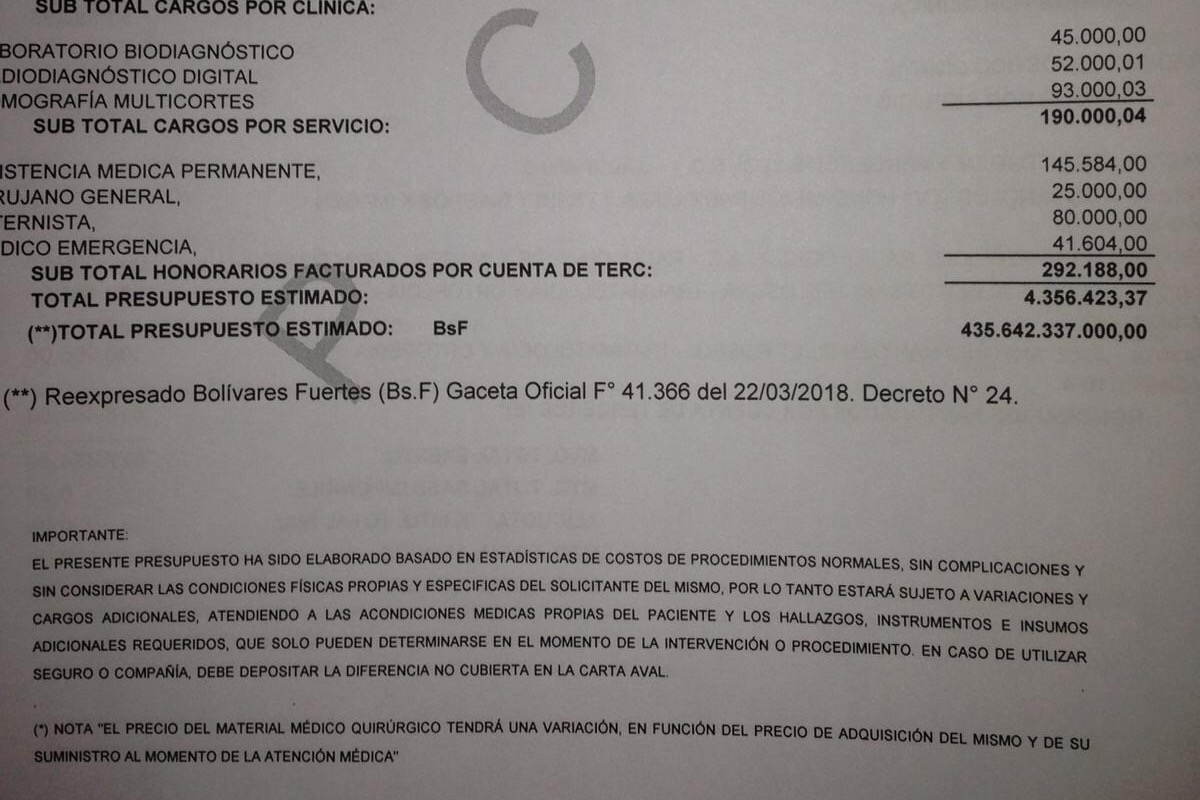

Los gastos de la clínica son 6.000$ mas 6.000$ de los honorarios profesionales del médico cirujano que lo operará, serán transferidos a una cuenta en los Estados Unidos de dicho médico cirujano o retirados y depositados en la misma.

Adjuntas las fotos del suceso, cuentas medicas, y otras documentaciones que respaldan el suceso.

Los gastos de la clínica son 6.000$ mas 6.000$ de los honorarios profesionales del médico cirujano que lo operará, serán transferidos a una cuenta en los Estados Unidos de dicho médico cirujano o retirados y depositados en la misma.

Adjuntas las fotos del suceso, cuentas medicas, y otras documentaciones que respaldan el suceso.